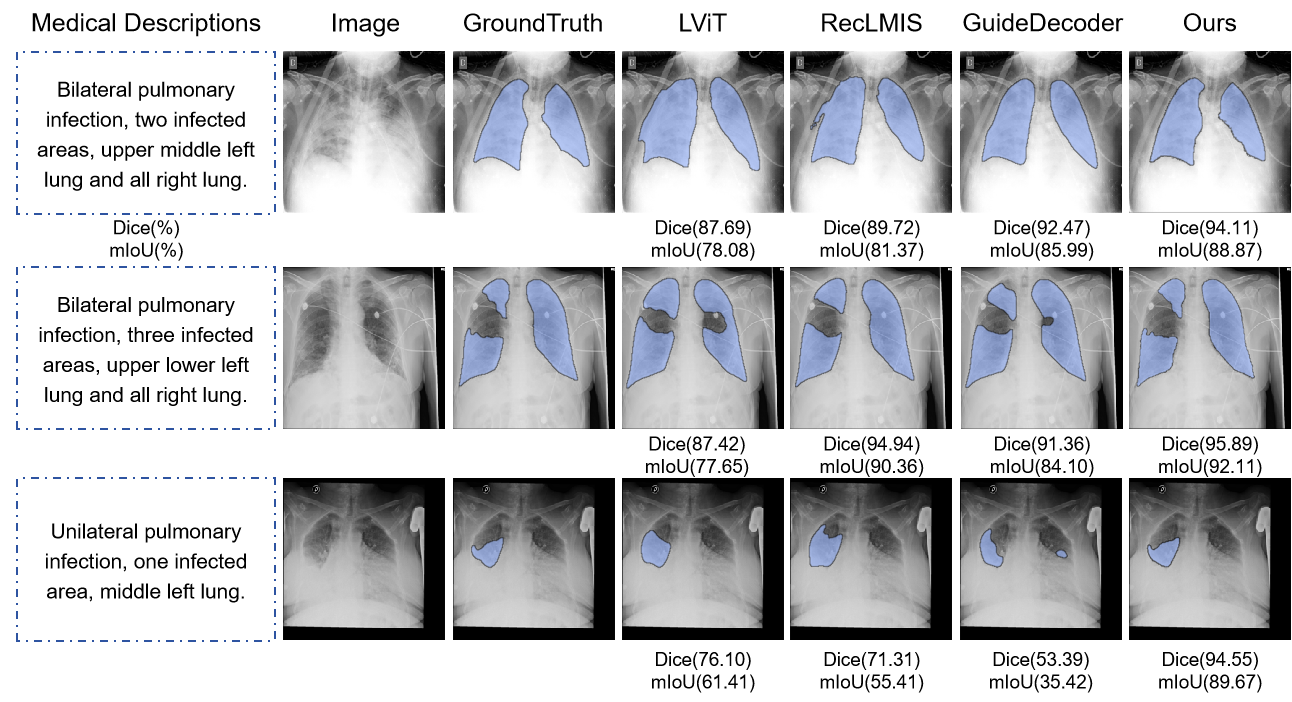

4.3 Comparison with SOTA

We compare our network with several mainstream CNN-based models, transformer-based models, medical segment anything based (MedSAM) segmentation models and hybrid architectures. We categorize the models based on whether they utilize text input. Table LABEL:tab1_comparisons_with_SOTA shows that medical descriptions generally improve segmentation performance, showing the necessity of the MRIS task. As shown in Fig. 4 and Fig. 5, we conducted a visualization analysis of main comparison with SOTA Method on main comparison with SOTA Method. The NTP-MRISeg we proposed achieves accurate segmentation performance. Whether on the QaTa-COV9 or MosMedData+, our model has outperformed previous SOTA. Earlier models, such as ConViRT[31] and TGANet[32], employ traditional CNN structures but fail to fully utilize textual advantages due to insufficient inter-modal fusion. Recent models, including the hybrid architecture of the previous best-performing model LViT[5] and similar approaches like SGSeg[7] and GuideDecoder[6], have achieved improved performance while following comparable architectural designs. TGCAM[8] even achieved the previous SOTA with 90.60 Dice and 82.81 mIoU on QaTa-COV19 dataset and 77.82 Dice 63.69 mIoU on MosMedData dataset, respectively. Pure transformer architectures RefSegformer[47] and DMMI[22] were also applied to MRIS, but their results were unsatisfactory due to limited adaptability to medical scenarios. Our NTP-MRISeg maintains the simplicity of pure transformer architecture while incorporating MRIS-specific optimizations such as NkTP and HET. The evaluation results on both datasets demonstrate excellent performance, achieving 91.10 Dice and 83.66 mIoU on the QaTa-COV19 dataset and 79.18 Dice and 65.54 mIoU on the MosMedData+ dataset, respectively. Particularly on the MosMedData dataset, where lesions in CT images are often more subtle than in X-ray images, our model shows sensitivity to such changes at the token level, achieving improvements of 1.36 Dice and 1.85 mIoU over the previous SOTA, respectively.